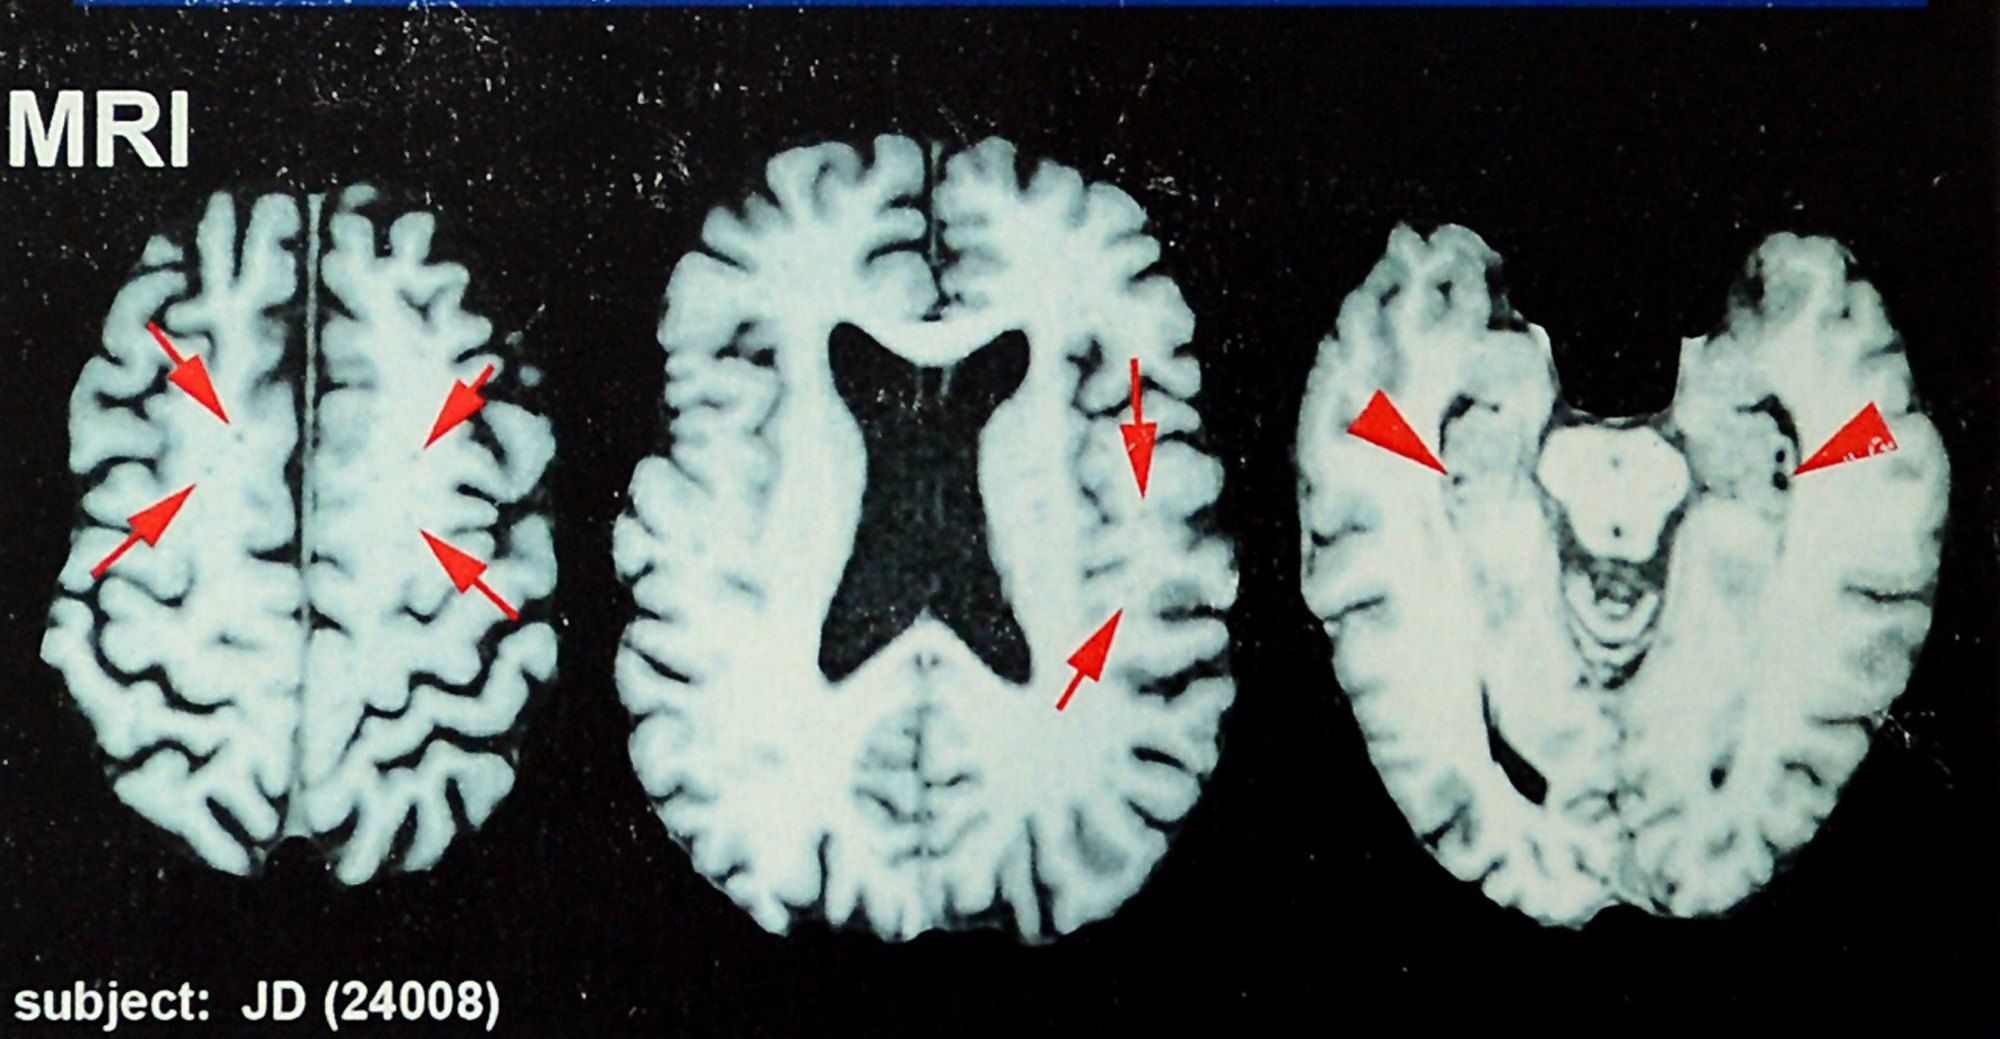

What the doctors are talking about is a practice called “race-norming,” which supposedly protects against a misdiagnosis. But it assumes because Black players on average start their football careers at a lower level of cognitive functioning than white players, the Black players must show a bigger cognitive drop to get compensation.